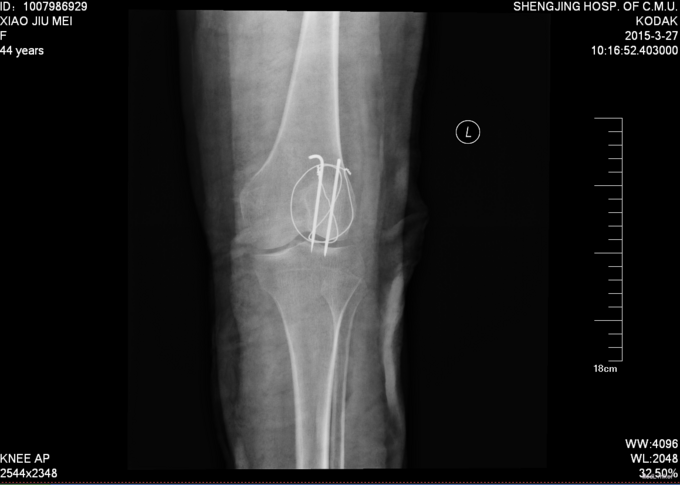

诊断:左髌骨骨折 患者入院后见患肢肿胀明显,给予患肢石膏固定抬高位,冷敷,甘露醇消肿等对症治疗,带患肢出现褶皱试验阳性后,CSEA下行左髌骨骨折切口复位张力带内固定术,术后患者肿胀明显,给予,消肿,冷敷,患肢抬高等对症治疗。患者每天换药观察切口愈合情况,无红肿及渗出,待伤口12天后予以拆线治疗,予以出院,给予康复处方。